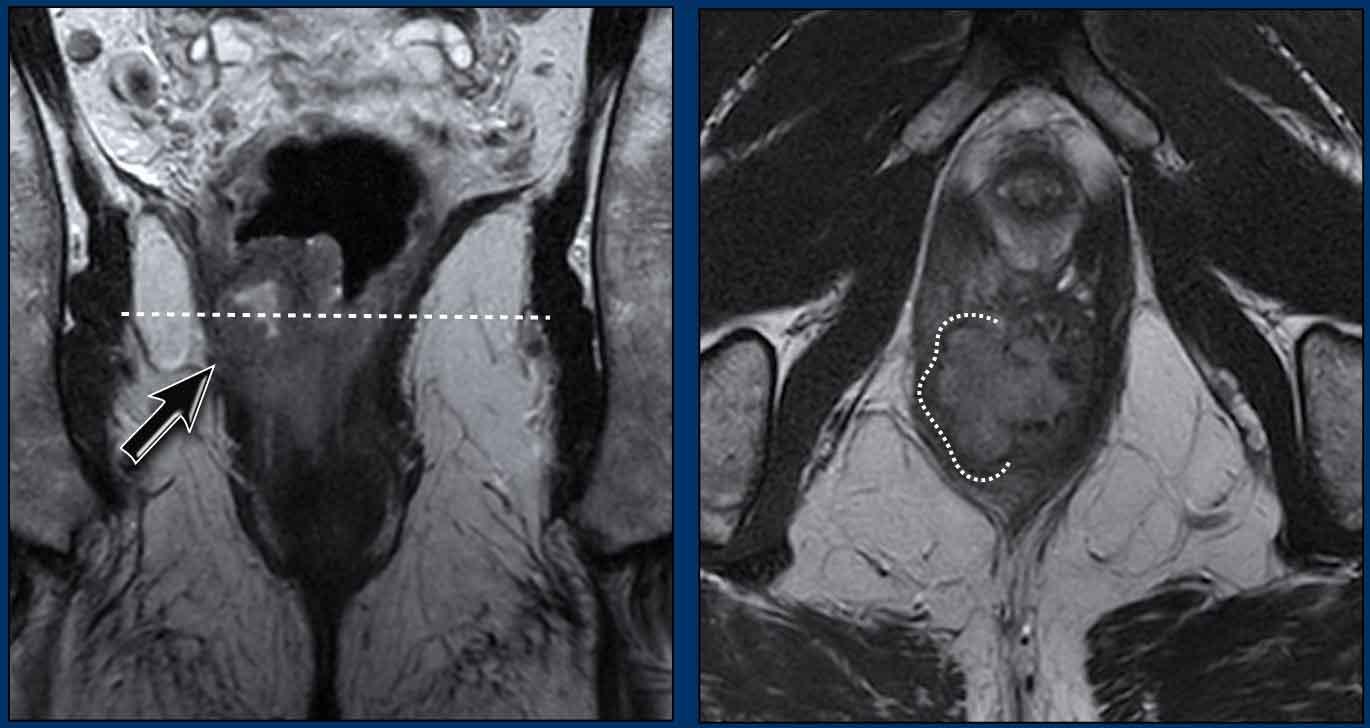

Hình ảnh

Đây là hình ảnh ung thư hậu môn trước hóa xạ trị.

Hình ảnh sau CRT

Ghi nhận đáp ứng hoàn toàn với chỉ một vùng xơ hóa mỏng nhỏ tại vị trí khối u cũ ở vị trí 1-3 giờ trong cơ thắt trong (mũi tên).

Không có dấu hiệu hạn chế khuếch tán (cuộn ảnh).

Phần còn lại của cơ thắt trong cho thấy tín hiệu trung gian đến cao mờ nhạt, biểu hiện phù nề do xạ trị (không có hạn chế khuếch tán).

Ghi nhận tái phát tại chỗ 2 năm sau khi hoàn thành CRT.

Lưu ý rằng tổn thương tái phát có kích thước lớn hơn khối u nguyên phát.

Cần thực hiện phẫu thuật cắt bỏ bụng-tầng sinh môn mở rộng sau khi xạ trị lại để cứu vãn trường hợp tái phát này.